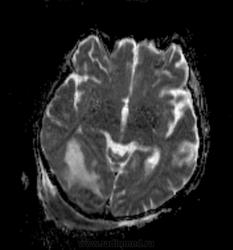

Мужчина проходит курс химиотерапии по поводу Т-клеточной лимфомы с первичным поражением кишечника (гистологическая верификация). За последний месяц - появление множественных очагов в печени, а также необычных изменений в голове.

- бесформенное образование в мягких тканях затылочной области, накапливающее контраст;

- утолщение твердой мозговой оболочки в той же области с накоплением контраста по пахименингиальному типу;

- отек прилежащей мозговой ткани с геморрагическими изменениями в коре, сопровождающийся масс-эффектом.

Мое мнение это лимфома кожи с прорастанием (если так можно сказать) через перфорирующие сосуды в ТМО, с кровоизлияниями в коре за счет повреждения сосудов. Либо это лептоменингальнаые проявления лимфомы. Больше на ум ние чего не приходит. Хотелось бы услышать мнение более опытных специалистов. но все почему-то молчат...

Я тоже думаю, что это лимфома. Думаю, не так важно, прорастает ли она из мягких тканей в мозговые оболочки, или наоборот. Только поражение мозговой оболочки - это пахи-, а не лептоменингиальные изменения.

В таком случае изменения в мозговой ткани - это отек, обусловленный нарушением венозного оттока по поверхностным венам; думаю, вкупе с геморрагическими изменениями этот отек можно квалифицировать как венозный инфаркт.